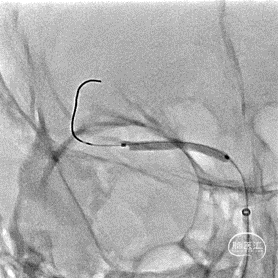

选取工作角度造影,测量病变长度。

微导丝辅助微导管通过闭塞段,以赛诺神畅Neuro LPS-1.5-15mm球囊分次扩张闭塞段。

球扩后造影见闭塞段恢复正向血流M1段远端夹层表现。

(2倍速播放)

沿微导丝输送赛诺神畅 NOVA颅内药物球扩支架2.25*20mm支架到位,支架输送顺利,全过程无明显张力变化。

6atm缓慢扩张释放支架。

释放支架后造影见支架中段稍有残留狭窄,以8atm缓慢再扩张,残留狭窄消失。